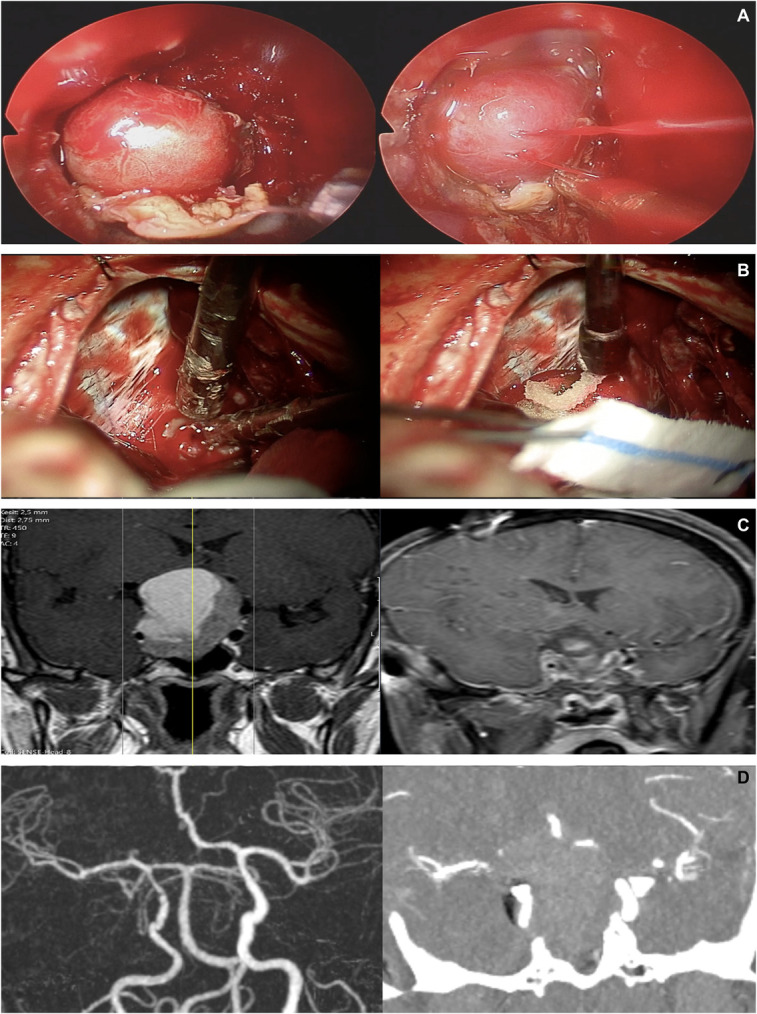

背景与目的:内窥镜鼻内手术(EES)因其全景性和详细的解剖定义而成为治疗鞍区和鞍旁病变的首选方法。本研究旨在回顾EES的主要动脉损伤,这是一种罕见但严重的并发症,具有高死亡率和发病率。方法:回顾性分析1997年8月至2024年2月在我中心/神经外科进行的5640例EES手术中的15例患者。该研究侧重于围手术期和术后管理策略,强调使用氧化再生纤维素(Surgicel®)/明胶凝血酶基质(Floseal®)和多学科合作来实现止血。结果:大动脉损伤发生率为0.2%,患者平均年龄38.4岁,男女比例为10:5。最常见的肿瘤是腺瘤(n = 7)和脊索瘤(n = 5)。6例患者中最常见的出血动脉分别是颈内动脉海绵状段和颈门旁动脉。10例患者出现低流量出血,5例患者出现高流量出血,其中4例复发(P < 0.05)。3例颈动脉段高流量出血患者行数字减影血管造影置入支架或线圈栓塞,1例高流量出血患者行数字减影血管造影监测脑血流。1例患者在随访第14个月时死于心肌梗死,1例患者出现左偏瘫。结论:该研究强调了术前计划、外科专业知识和多学科团队合作在EES中处理主要动脉损伤的重要性。作者主张发展标准化的治疗算法,以改善这些患者的预后。这些发现弥补了EES中处理颈内动脉损伤的有限文献,强调了持续研究和算法开发的必要性。

Results: The incidence of major arterial injury was 0.2%, with a mean patient age of 38.4 years and a female-to-male ratio of 10:5. The most common tumors were adenomas (n = 7) and chordomas (n = 5). The most commonly bleeding arteries in 6 patients each are the cavernous segment of the internal carotid artery and the paraclival carotid artery. Low-flow bleeding was observed in 10 of our patients, while high-flow bleeding was seen in 5 patients, 4 of whom were recurrent cases ( P < .05). In 3 patients with high-flow bleeding from segments of the carotid artery, digital subtraction angiography was performed for stent placement or coil embolization, while in 1 patient with high-flow bleeding, digital subtraction angiography was used for monitoring cerebral blood flow. One of our patients died of a myocardial infarction at the 14th month of follow-up and 1 of our patients developed left-hemiparesis.